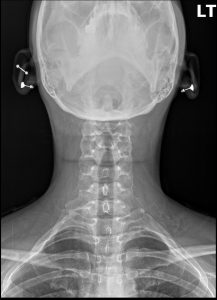

Anteroposterior (AP) and lateral cervical spine radiographs were performed. The AP view clearly demonstrates the presence of bilateral accessory ribs originating from the transverse processes of the C7 vertebra. The left-sided cervical rib is more developed and articulates with the first thoracic rib via a fibrous band, a finding known as a pseudoarthrosis. The remainder of the cervical spine shows preserved vertebral body heights and disc spacing. There is a mild straightening of the expected cervical lordosis, which may be secondary to protective muscle splinting.

Bilateral Cervical Ribs, with anatomical features correlating to clinical symptoms of left-sided neurogenic *Thoracic Outlet Syndrome (TOS)*.

Identification: An osseous structure arising from the C7 transverse process, seen most clearly on an AP cervical or chest radiograph.

Laterality:Â May be unilateral or bilateral, but symptoms are often unilateral even when the anomaly is bilateral.

Morphology: Can range from a small, incomplete bony process to a full rib that articulates with the first thoracic rib.

Association:Â Its presence is a classic and primary cause of true neurogenic TOS.